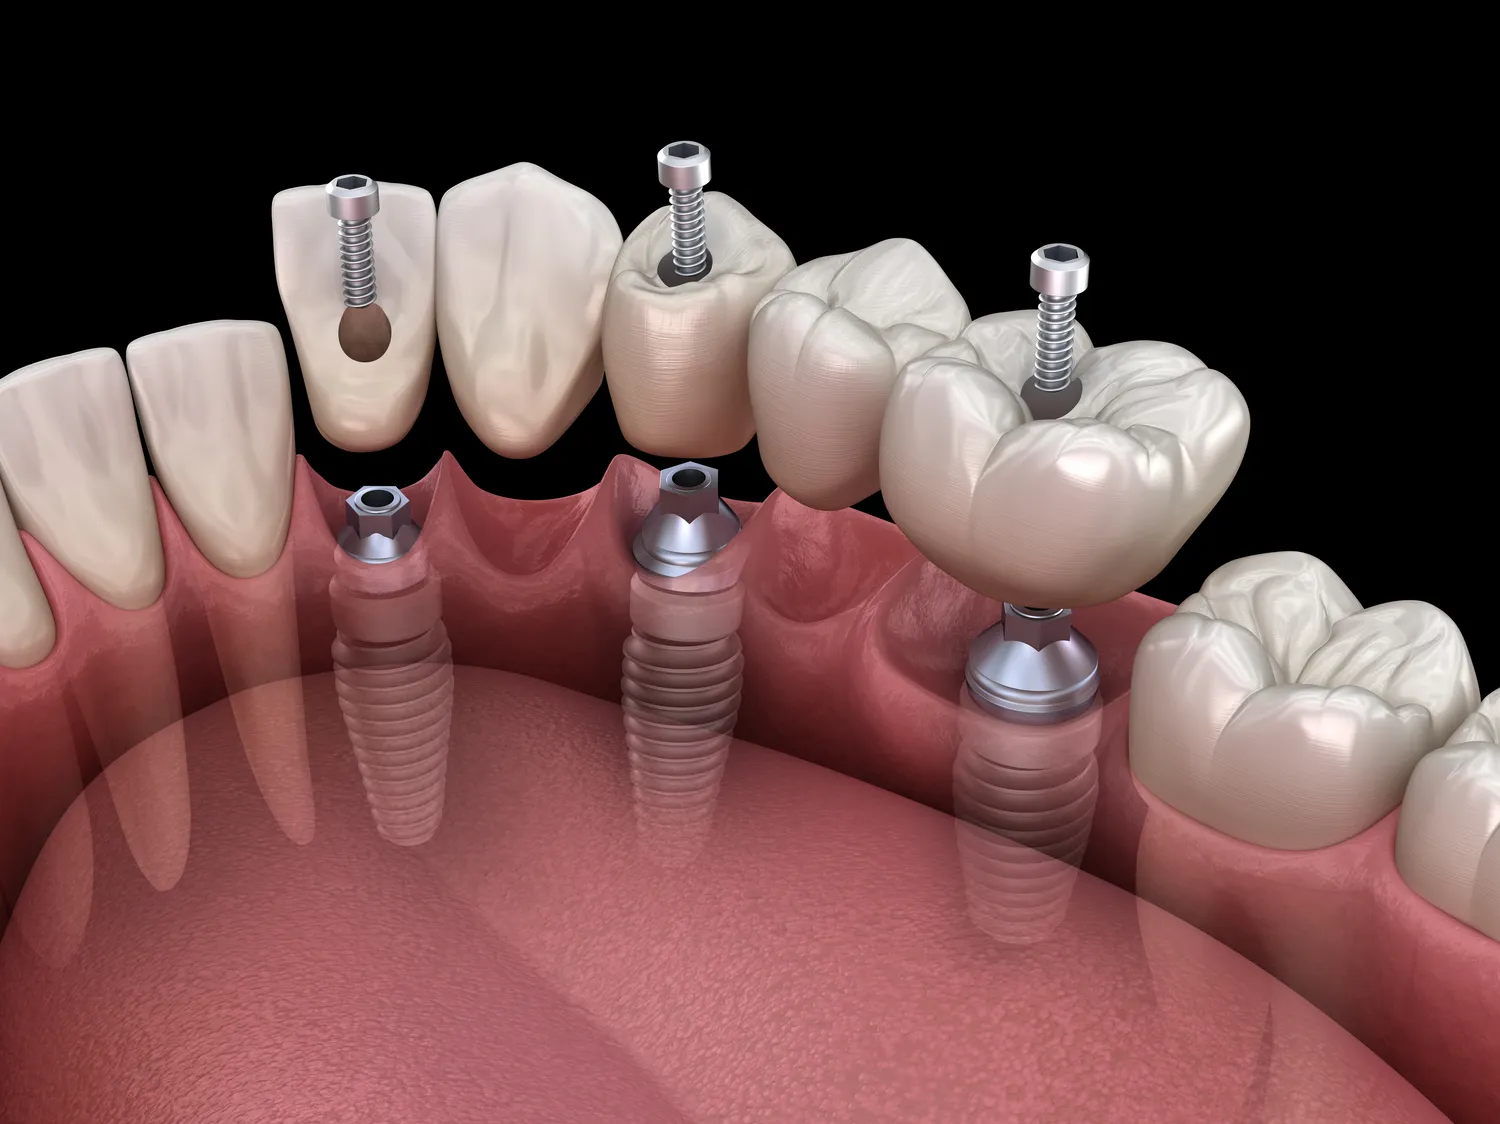

Implanty dentystyczne mają wiele zalet, które przyciągają pacjentów do ich stosowania jako alternatywy dla tradycyjnych protez czy mostków. Przede wszystkim zapewniają one trwałość i stabilność; dobrze osadzone implanty mogą służyć przez wiele lat, a nawet dekad. Dzięki nim pacjenci mogą cieszyć się pełnią funkcji żucia oraz swobodą mowy bez obaw o przesuwanie się protez. Kolejną istotną zaletą jest estetyka; implanty wyglądają bardzo naturalnie i są dostosowane do koloru pozostałych zębów pacjenta, co pozwala uzyskać harmonijny uśmiech. Dodatkowo stosowanie implantów pomaga w zachowaniu struktury kości szczęki; brak zębów prowadzi do zaniku kości, a implanty stymulują jej regenerację. To ważny aspekt zdrowotny, który wpływa nie tylko na wygląd twarzy, ale także na ogólne samopoczucie pacjenta. Warto również zauważyć, że implanty nie wymagają szlifowania sąsiednich zębów jak ma to miejsce w przypadku mostków, co pozwala zachować zdrowe tkanki zębowe. Dlatego coraz więcej osób decyduje się na tę formę leczenia stomatologicznego jako długoterminowe rozwiązanie problemu utraty zębów.

Proces gojenia po wszczepieniu implantu zęba jest kluczowym etapem całego leczenia i może trwać od kilku tygodni do kilku miesięcy w zależności od indywidualnych predyspozycji pacjenta oraz rodzaju zastosowanego implantu. Bezpośrednio po zabiegu pacjent może odczuwać ból oraz obrzęk w okolicy wszczepu; te objawy są normalne i zazwyczaj ustępują po kilku dniach dzięki zastosowaniu leków przeciwbólowych oraz zimnych okładów. W tym czasie ważne jest przestrzeganie zaleceń lekarza dotyczących diety oraz higieny jamy ustnej; zaleca się unikanie twardych pokarmów oraz stosowanie miękkiej diety przez kilka pierwszych dni po zabiegu. Regularne kontrole u stomatologa są niezbędne dla monitorowania procesu gojenia; lekarz może ocenić stan implantu oraz otaczających tkanek i w razie potrzeby wdrożyć dodatkowe działania terapeutyczne. Po zakończeniu etapu gojenia następuje kolejny krok – osadzenie korony na implancie, co przywraca pełną funkcjonalność żucia oraz estetykę uśmiechu. Warto pamiętać, że odpowiednia pielęgnacja implantu oraz regularne wizyty kontrolne są kluczowe dla jego długowieczności i zdrowia jamy ustnej.